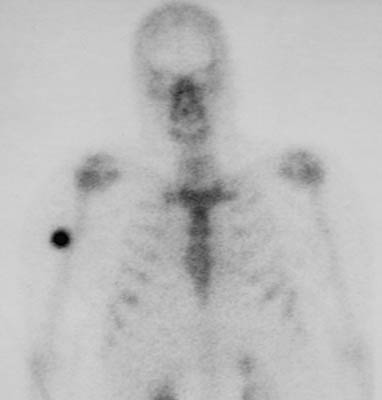

| This axial T2 weighted MRI scan shows a rounded tumor-like mass that is an area of myositis ossificans in skeletal muscle adjacent to the humerus. There is a central core of exuberant granulation tissue surrounded by a zone of reactive bone formation. The lesion appears as a discrete "hot spot" in soft tissue in the bone scan below. |